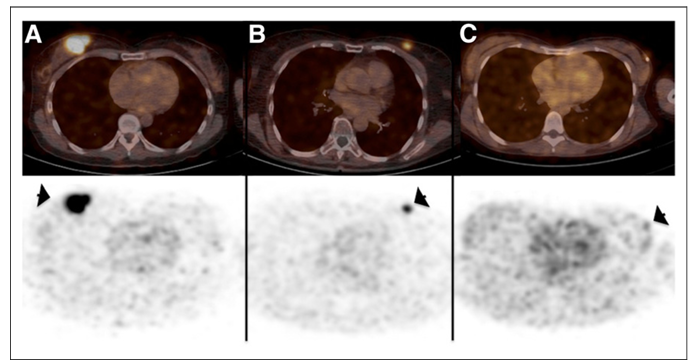

圖三、PET/CT 圖像(上圖)和 PET 圖像(下圖)顯示原發(fā)性乳腺癌病灶(箭頭)中68-GaNOTA-Anti-HER2 VHH1的攝取。(A) 14號(hào)患者的示蹤劑攝取最高(SUV 平均值,11.8)。(B) 15號(hào)患者顯示中度示蹤劑攝取,仍具有很高的腫瘤-背景比(SUV 平均值,4.9)。(C)6號(hào)患者成像結(jié)果顯示沒有攝?。⊿UV 平均值,0.9),CT圖像的腫瘤區(qū)域用箭頭指示。

HER2 納米抗體示蹤劑68-GaNOTA-Anti-HER2 VHH1在I期臨床試驗(yàn)中取得了令人鼓舞的結(jié)果,68-GaNOTA-Anti-HER2 VHH1在腫瘤中的積累水平明顯超過了背景值,且在HER2 陽性轉(zhuǎn)移灶中有高積累。因此,該示蹤劑順利進(jìn)入了II 期臨床研究,目的是評(píng)價(jià)乳腺癌患者腦轉(zhuǎn)移瘤對(duì)該示蹤劑的攝取情況 (圖三)(NCT03331601)3?;?8-GaNOTA-Anti-HER2 VHH1的優(yōu)良性能,Precirix公司進(jìn)而開發(fā)了[131I]-SGMIB Anti-HER2 VHH1示蹤劑,現(xiàn)正在進(jìn)行臨床I 期試驗(yàn),旨在評(píng)價(jià)該示蹤劑的安全性、耐受性及有效劑量(NCT02683083)4。此外,另一款納米抗體成像劑99mTc-NM-02正在進(jìn)行I期臨床研究 (NCT04040686)5,10位乳腺癌患者注射 3-12 MBq/kg 99mTc-NM-02, 無不良反應(yīng)報(bào)道,且99mTc-NM-02的攝取與HER-2的表達(dá)呈正相關(guān)。近期,北京大學(xué)臨床腫瘤學(xué)院研發(fā)的99mTc-MIRC208也正在臨床實(shí)驗(yàn)中,共有200位受試者,旨在研究納米抗體示蹤劑99mTc-MIRC208對(duì)HER2陽性患者成像的可行性及特異性(NCT04591652)。